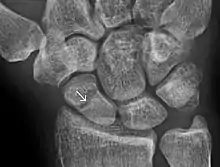

A subtle scaphoid fracture

Radiolucency around a 12 days old scaphoid fracture that was initially barely visible.[13]